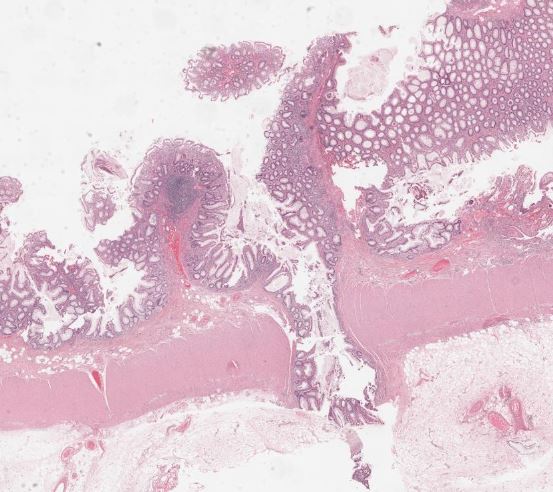

67-year-old female with odynophagia. #GIpath #pathresidents #PathTwitter